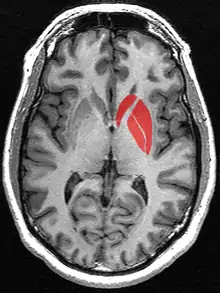

![]() Putamen (in red) shown within the brain | |

The putamen (/pjuˈteɪmən/; from Latin, meaning "nutshell") is a round structure located at the base of the forebrain (telencephalon). The putamen and caudate nucleus together form the dorsal striatum. It is also one of the structures that compose the basal nuclei. Through various pathways, the putamen is connected to the substantia nigra, the globus pallidus, the claustrum, and the thalamus, in addition to many regions of the cerebral cortex. A primary function of the putamen is to regulate movements at various stages (e.g. preparation and execution) and influence various types of learning. It employs GABA, acetylcholine, and enkephalin to perform its functions. The putamen also plays a role in degenerative neurological disorders, such as Parkinson's disease.

The putamen is a structure in the forebrain. Along with the caudate nucleus it forms the dorsal striatum. The caudate and putamen contain the same types of neurons and circuits – many neuroanatomists consider the dorsal striatum to be a single structure, divided into two parts by a large fiber tract, the internal capsule, passing through the middle. The putamen, together with the globus pallidus, makes up the lentiform nucleus. The putamen is the outermost portion of the basal ganglia. These are a group of nuclei in the brain that are interconnected with the cerebral cortex, thalamus, and brainstem. Basal ganglia include the dorsal striatum, substantia nigra, nucleus accumbens, and the subthalamic nucleus.